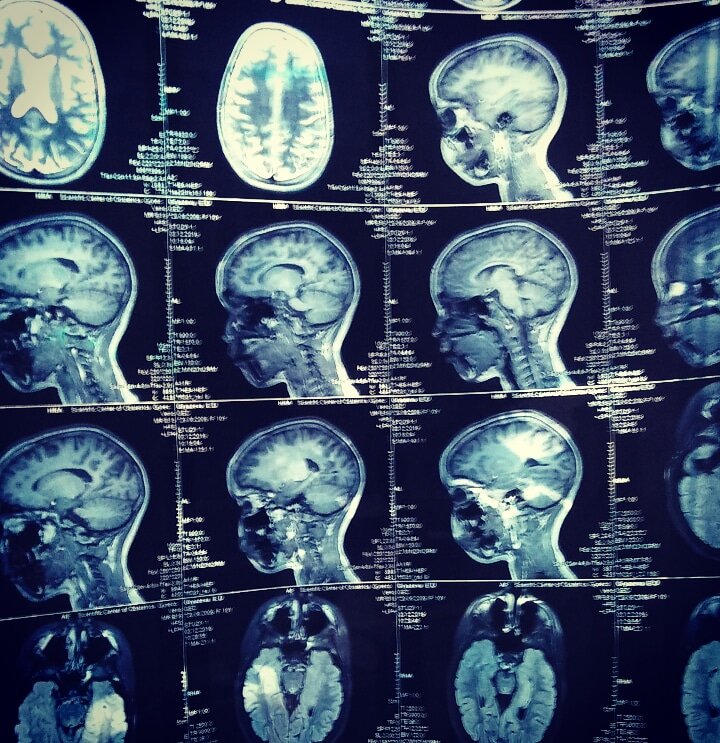

По итогу у Лизы выявлены: кортикальная дисплозия, неокклюзионная гидроцефалия, перивентикулярный глиоз, диффузные изменения гипофиза, кистозное расширение правой хориоидальной щели..

Но самое странное и непонятное, что все ЭТО с правой стороны, а по ээг-исследованиям эпи очаг с левой стороны...